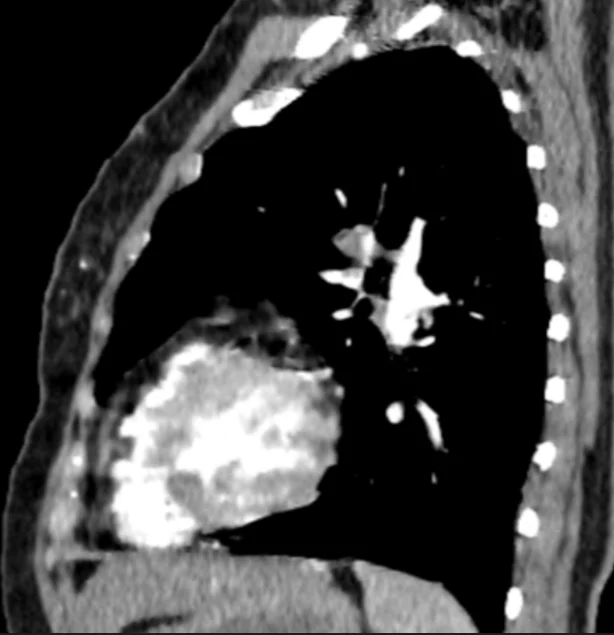

Figure 4. Sagittal Contrast – Enhanced CT Pulmonary Angiography (CTPA)

This sagittal reformatted contrast – enhanced CT image of the chest demonstrates a filling defect within the pulmonary arterial system, consistent with acute pulmonary embolism, along with parenchymal changes suggestive of pulmonary infarction.

Key Radiologic Findings:

- A hypodense intraluminal filling defect is seen within a pulmonary arterial branch, indicating embolic thrombus.

- The surrounding contrast outlines the clot, confirming intraluminal obstruction.

- There is a peripheral, wedge – shaped area of increased attenuation in the adjacent lung parenchyma. This appearance is characteristic of pulmonary infarction.

- The lesion is located in a dependent posterior region, which is typical for embolic infarcts.

Clinical Significance:

- This image demonstrates not only acute pulmonary embolism but also its complication – pulmonary infarction.

- Pulmonary infarction occurs due to: Prolonged vascular occlusion, impaired bronchial arterial compensation

- Patients with infarction may present with: Pleuritic chest pain, hemoptysis

Diagnostic Contribution:

This figure is important because it:

- Confirms the functional impact of embolism on lung tissue

- Differentiates simple embolism from complicated PE with infarction

- Helps explain clinical symptoms and severity

Radiology Insight (Expert Level):

- Pulmonary infarcts typically appear as: Peripheral wedge – shaped opacities, base abutting the pleura

- This corresponds to the classic: Hampton’s hump (on radiograph/CT)

- Sagittal views are particularly helpful for: Evaluating craniocaudal extent, Identifying posterior and basal lesions